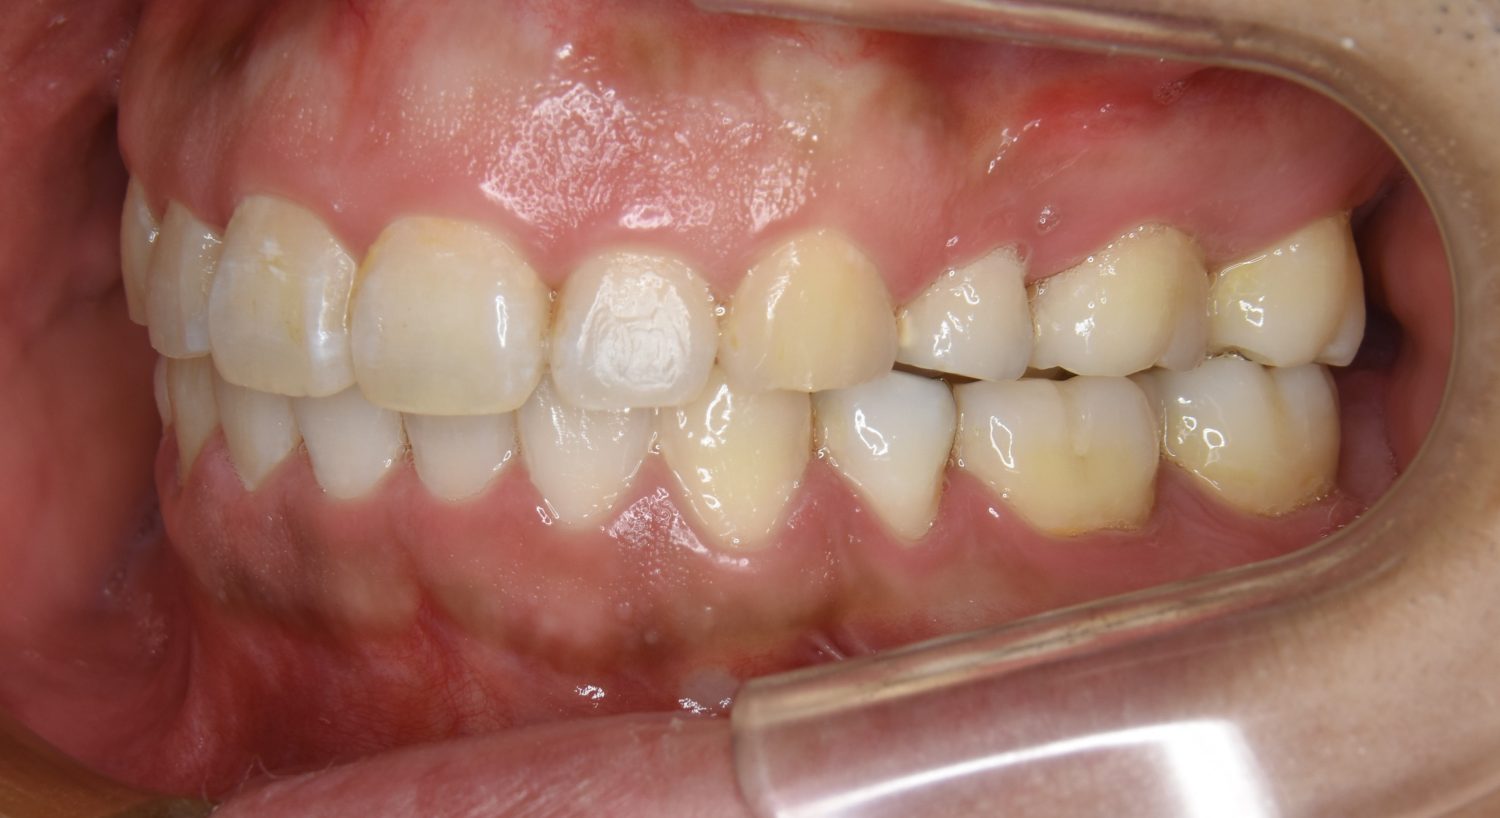

叢生の症例紹介②

Before

After

主訴

歯の凸凹を治したい。

治療内容

アライナー(インビザライン)にて非抜歯で治療を行いました。

治療費

1,150,000 円(税込)

治療期間

26ヶ月

通院回数

14回

想定されたリスク

※歯根吸収、歯肉退縮、歯髄壊死、顎関節症状

※アライナー(インビザライン)は日本の薬機法未承認の矯正装置であり、医薬品副作用被害救済制度の対象外となる場合があります。

丸山和宏先生

ピーススマイル矯正歯科

上下前歯部に叢生(凸凹)が認められる状態でした。歯列の遠心移動を行うことで機能面および審美面が改善されました。